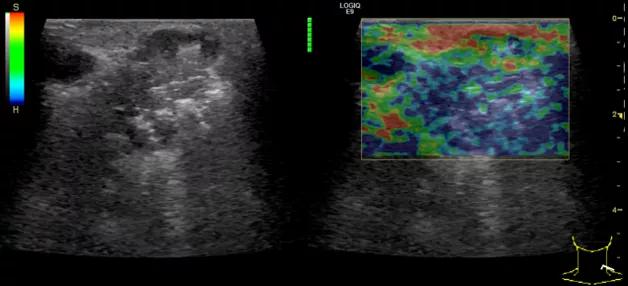

第三例是甲状腺癌患者,双侧甲状腺癌切除术后、碘治疗后一年余效果欠佳,超声显示左颈3区3枚低回声结节,穿刺示甲状腺乳头状癌转移。患者不愿意手术,希望采取局部治疗。对病灶进行液体隔离后采取热消融术,由于淋巴结较小,热消融一分钟左右完全灭活,术后增强影像显示没有脏器充填。

(病例3图例)